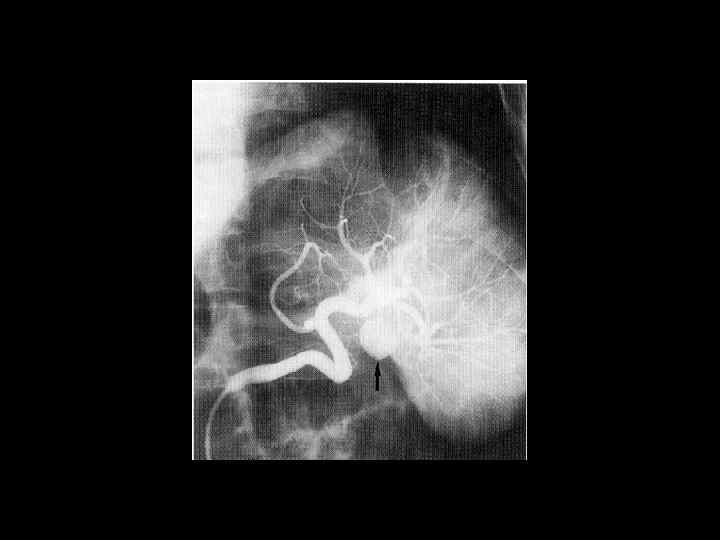

АКТУАЛЬНЫЕ ВОПРОСЫ РЕНТГЕНОЛОГИИ ЛУЧЕВАЯ ДИАГНОСТИКА ЗАБОЛЕВАНИЙ СЕЛЕЗЕНКИ Спленомегалия: Причины - Заболевания системы крови (гемолитические анемии, острые лейкозы, хронический миелоидный лейкоз, злокачественные лимфомы) - портальный цирроз печени - тромбоз селезеночной вены